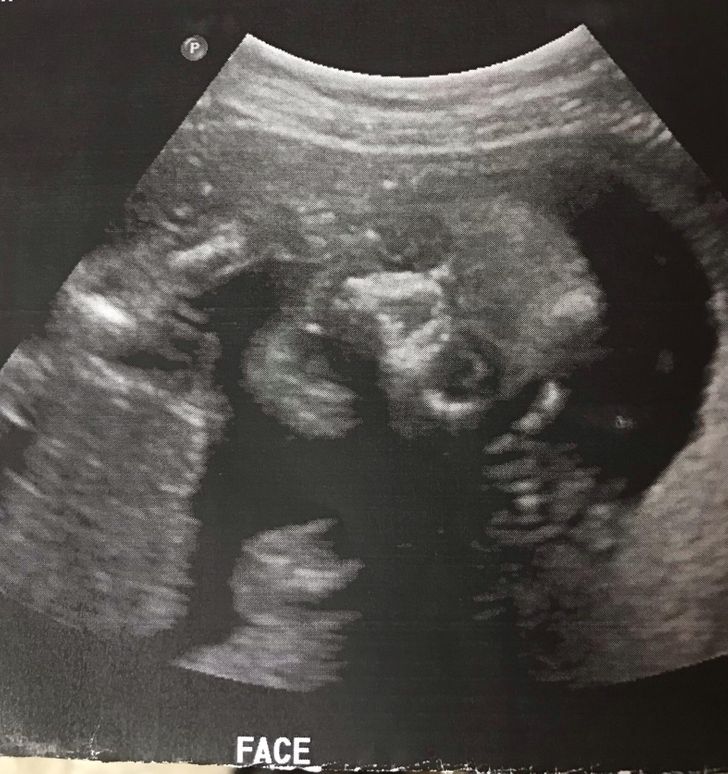

3. „Az egyik ultrahangos fotónk megijesztette a férjemet.”